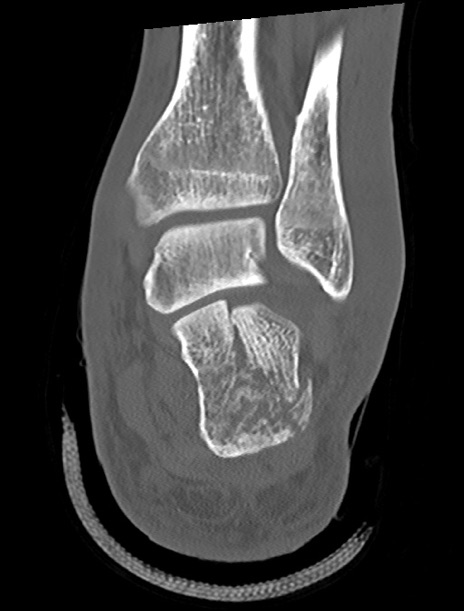

症例37 左足関節CT(冠状断像)

左足関節CT

矢状断像